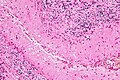

- Pseudopalisading - picket fence-like alignment of cells; long axis of cells perpendicular to interface with other structures/cells.

- Pseudopalisading of tumour cells (around necrotic regions) is seen in glioblastoma.

Pseudopalisading necrosis in a glioblastoma (WC/jensflorian)